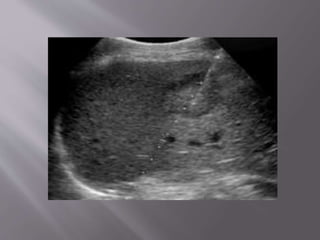

After the aspiration, the

needle (white line) and its

tip (double arrow) are

seen, but the lump is gone.

After the aspiration,the needle (white line) and its tip (double arrow) are seen, but the lump is gone.